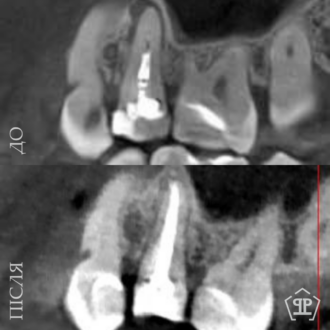

Роботи лікаря Все работы ⋅⋅⋅